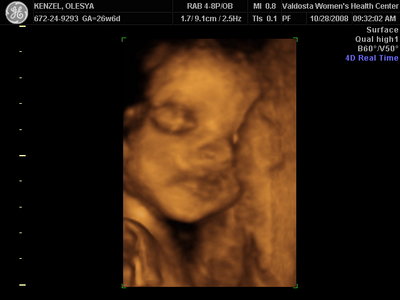

Еще одна Джианнка:

KENZEL,OLESYA_5.JPG [ 60.02 КБ | Просмотров: 1293 ]

Катюш, какой прикольный бутузик ! Олесь, после фотки средней - точно прям похожи!